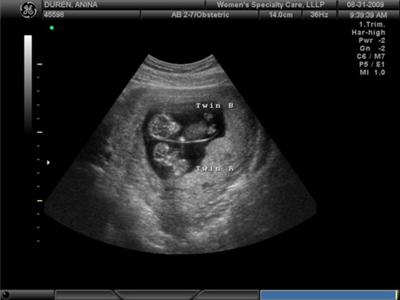

Une échographie à 11 semaines montrera les contours clairement visibles du petit homme. Sur un équipement haut de gamme avec une localisation particulièrement bonne du bébé, vous pouvez déjà déterminer son sexe. Cependant, les données peuvent être inexactes.

Avec une grossesse gémellaire (ou triple), le développement de chaque enfant est à peu près le même qu'avec une grossesse unique. Dans le même temps, les petits hommes peuvent différer sensiblement (de plusieurs millimètres) de croissance. C'est tout à fait normal.

Photo échographie: